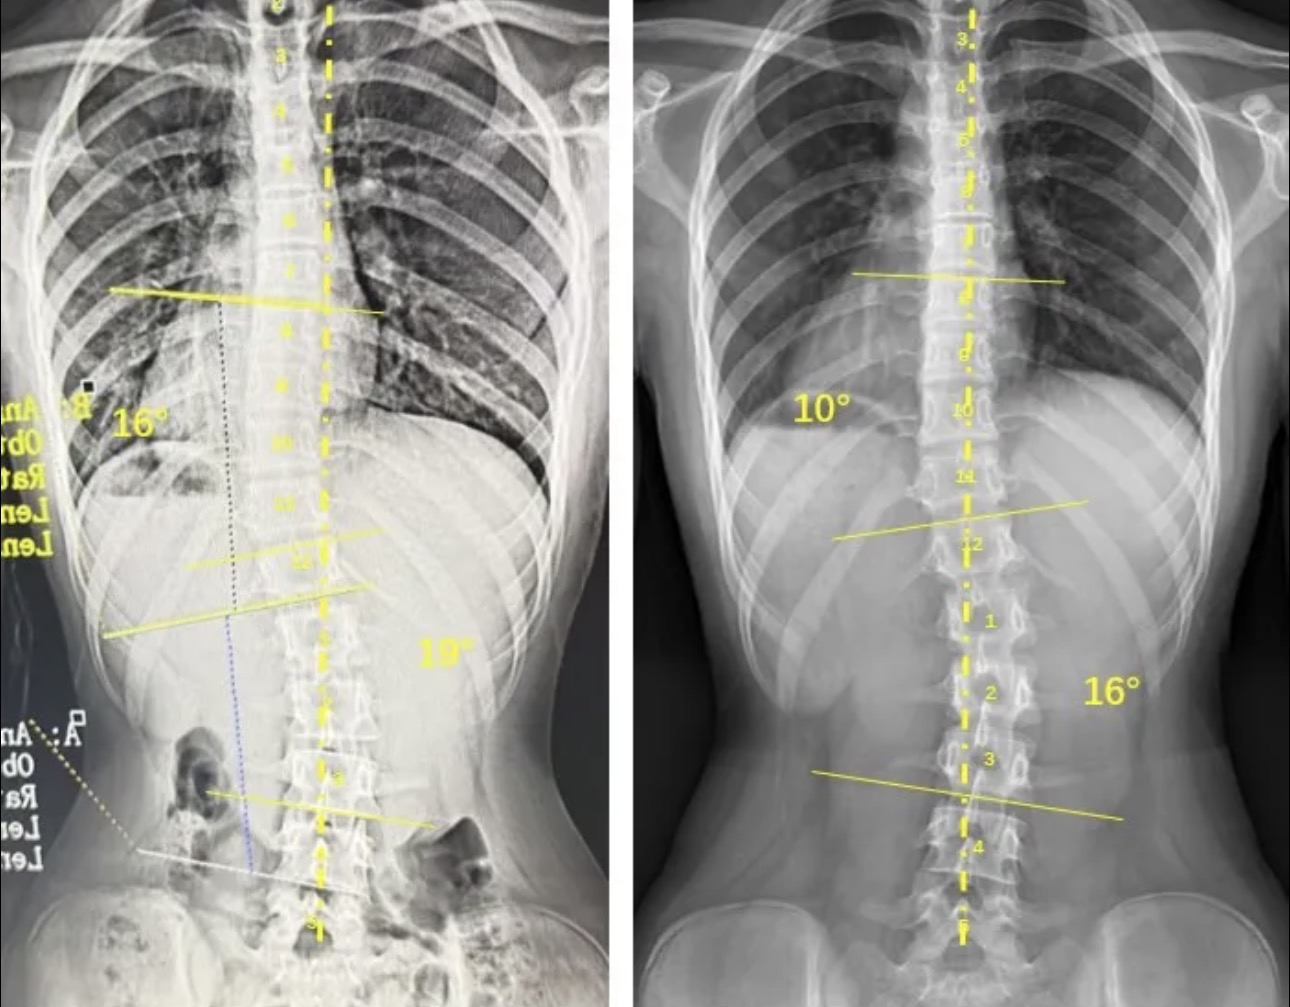

衷德脊柱,我们只关注侧弯保守治疗~

Zhongde Spine, bending no breaking ~